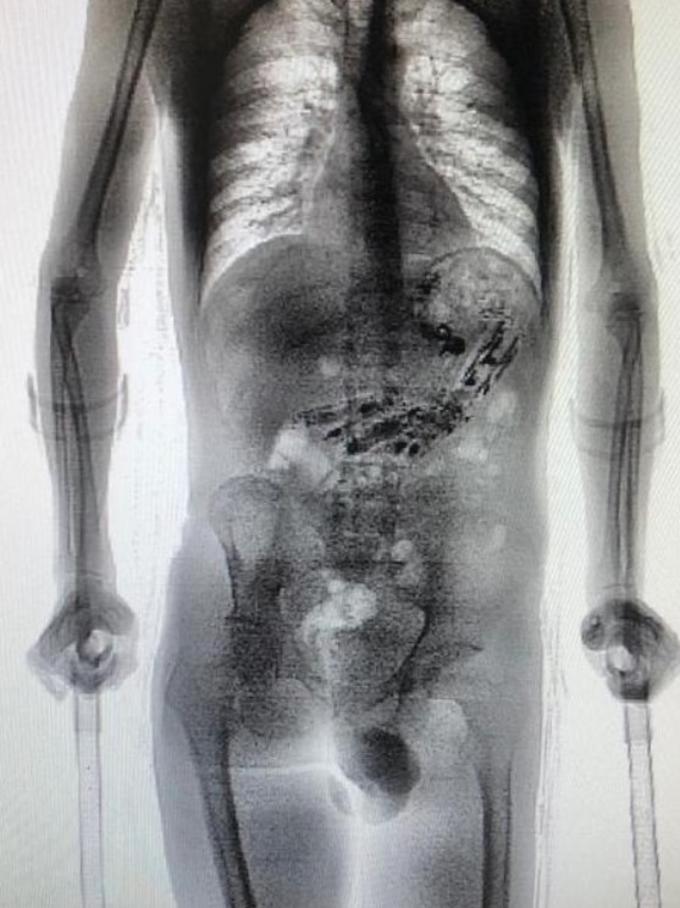

Um homem de 24 anos foi flagrado tentando entrar em uma penitenciária com 10 celulares e outros 52 objetos escondidos dentro do estômago nessa quarta-feira (16).

Entre eles estavam 10 mini celulares feitos de carbono, isqueiro, envelopes com drogas, chips e outros itens. O material foi encontrado no momento em que o interno voltava para a Colônia e precisou passar pelo scanner corporal.

Após o flagrante, ele foi encaminhado para um hospital em outra cidade e já passou por cirurgia para a retirada dos objetos. Assim que receber alta médica, ele será encaminhado novamente ao presídio e responderá por mais um crime.